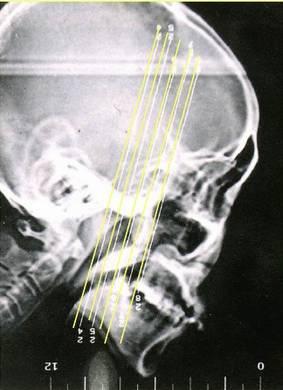

(二)检查

2、影像学检查:CT扫描显示窦口鼻道复合体或鼻窦粘膜病变。

• 副鼻窦X线检查,CT(冠状位、轴位)检查已常规应用。

正常鼻窦CT

鼻窦炎轴位CT